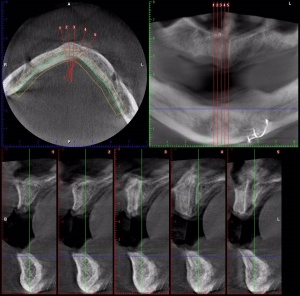

- Radiographs for Implants

- Guided Implant Placement